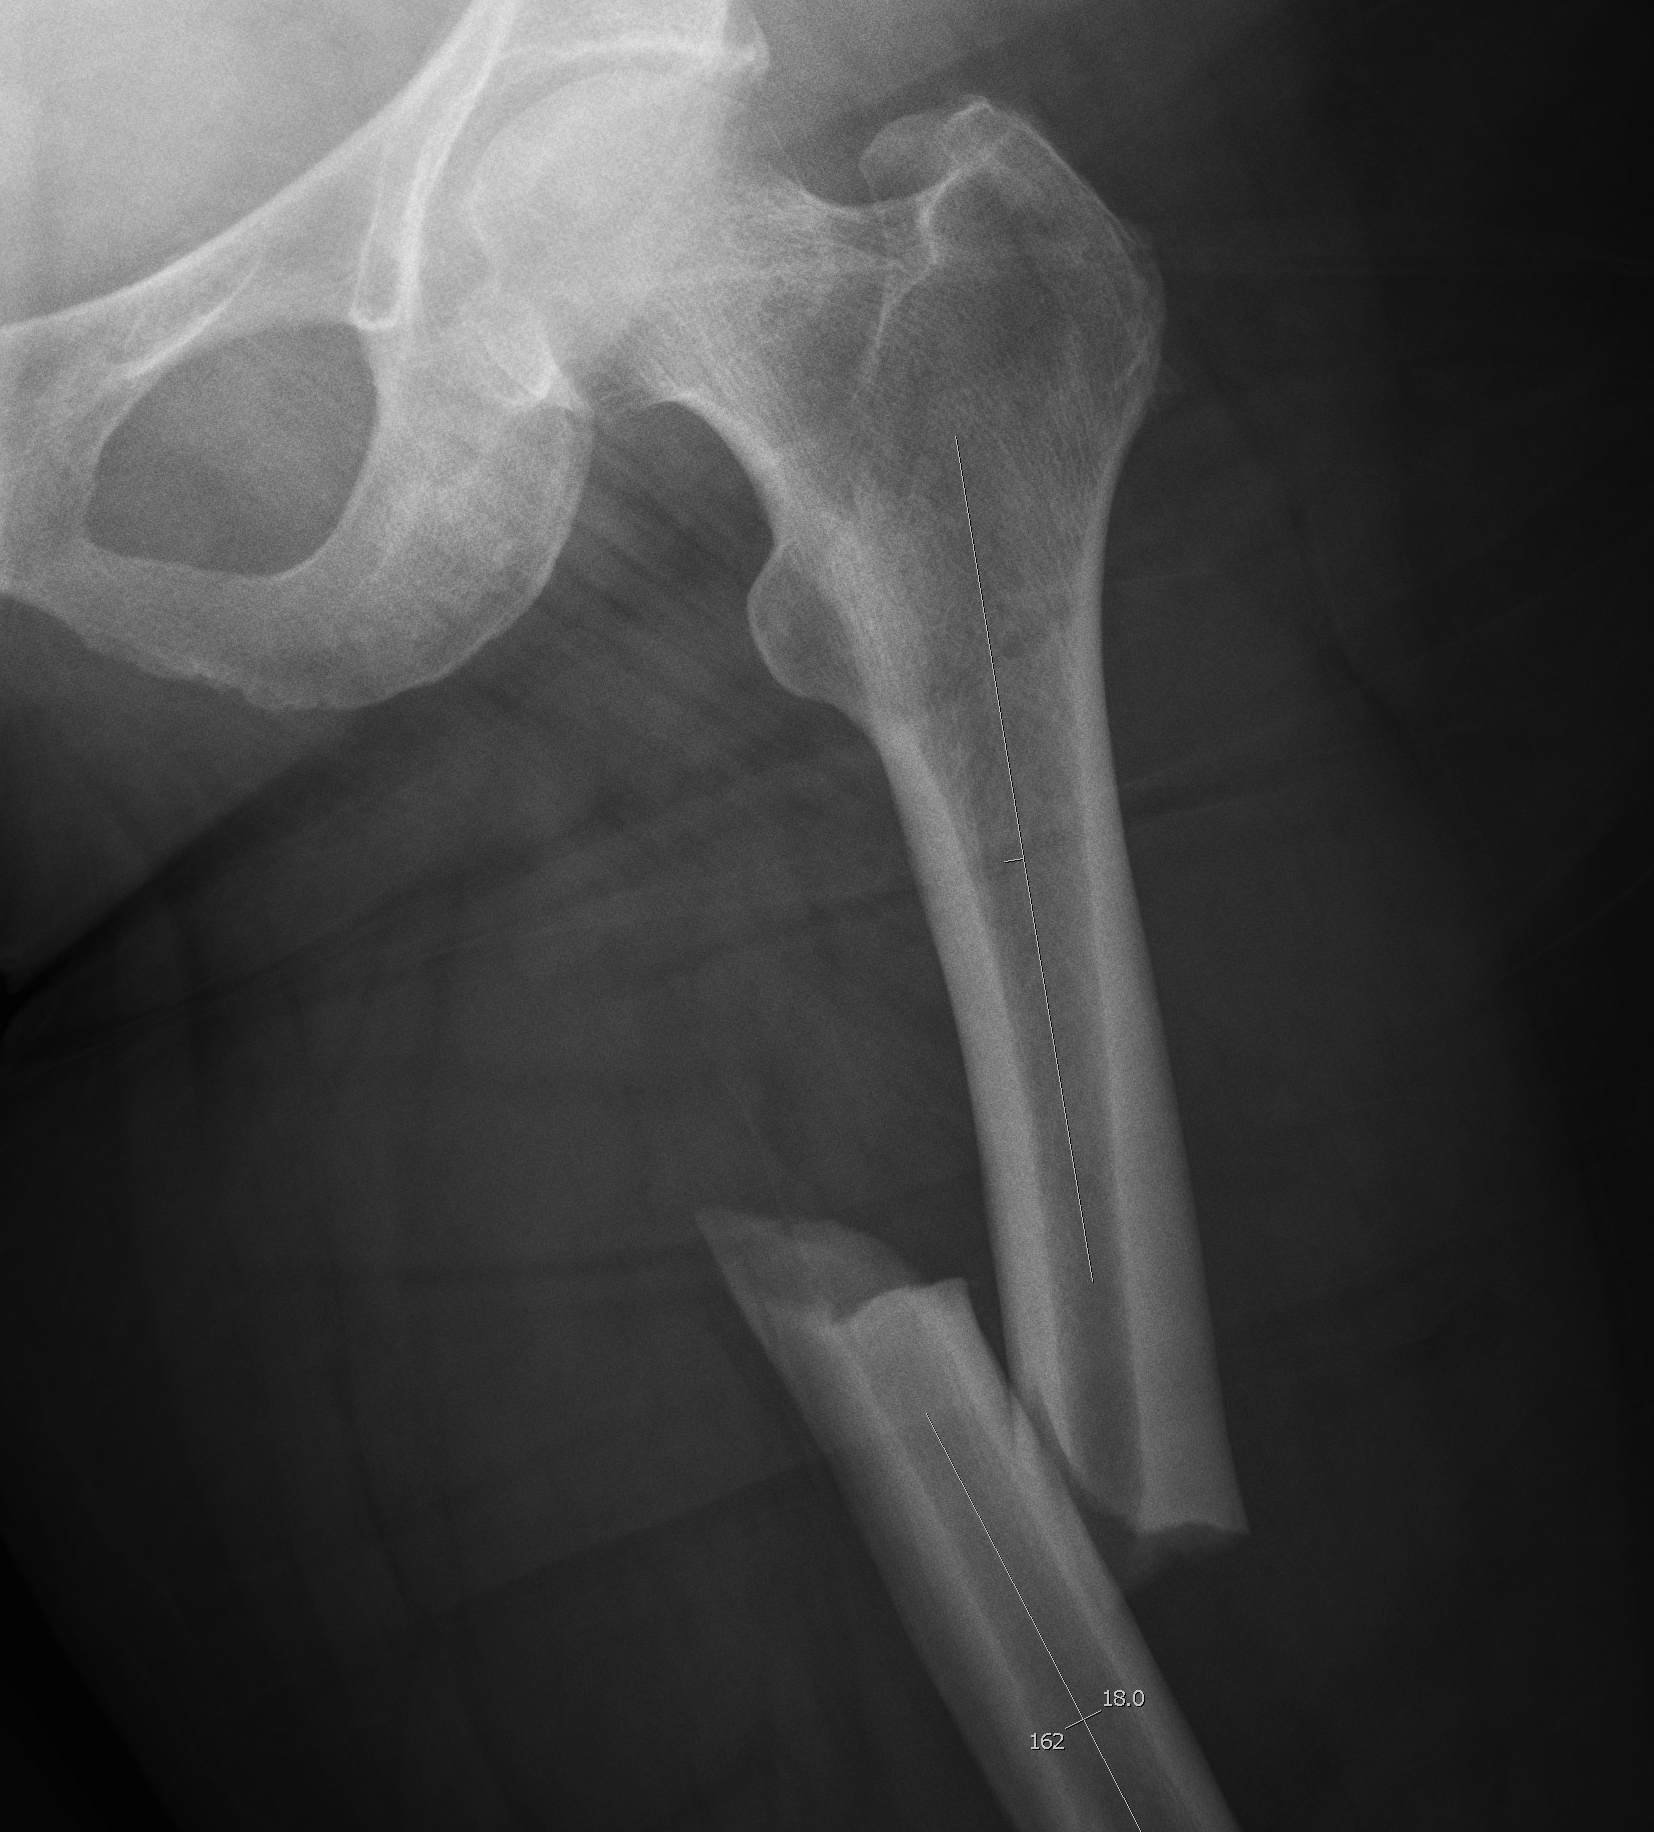

Atypical femoral fracture related to bisphosphonates

- reports of atraumatic bilateral femoral fracture

- seen in women taking bisphosphonates for more than 5 years

- insufficiency fracture

- characterised by short oblique subtrochanteric and diaphyseal fractures

- typically see lateral cortical thickening / sclerosis / beaking before the fracture

- must check contralateral femur if have a fracture

- xray any patient complaining of thigh pain

- recommend drug holidays to prevent this complication